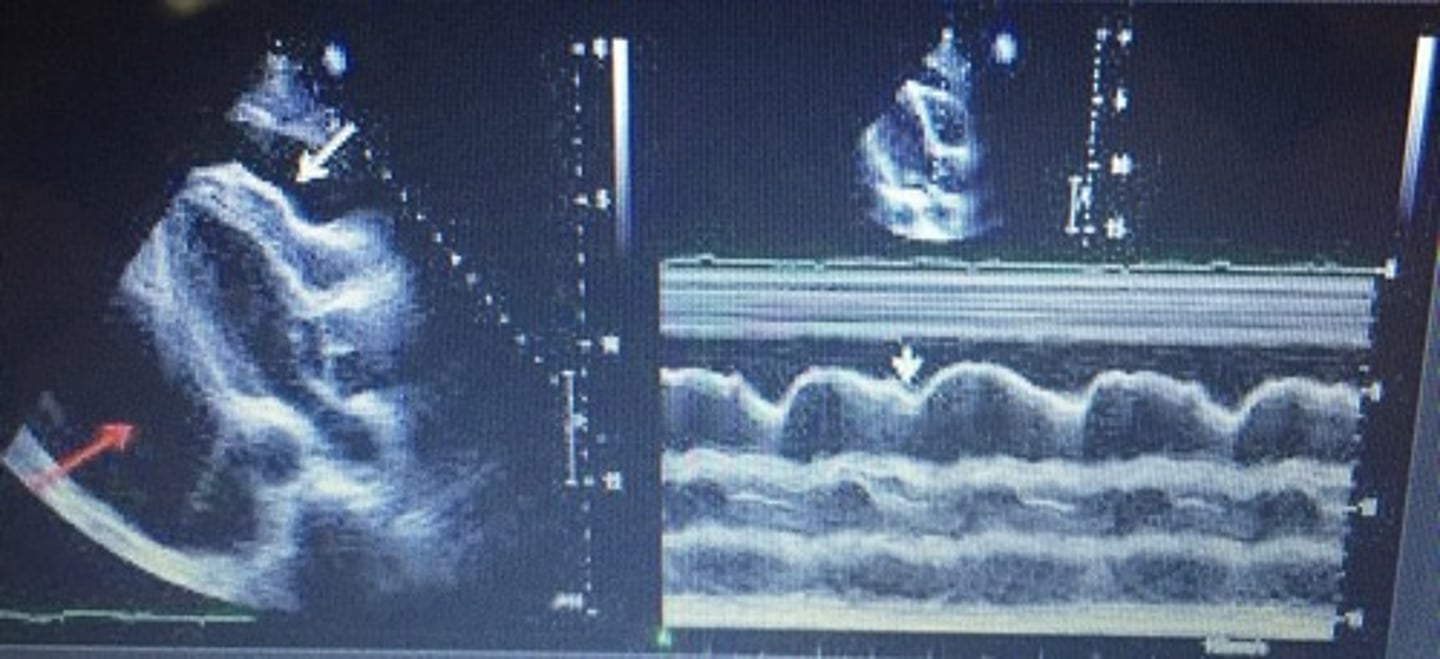

consistent with dyskinetic wall motion and appears as D-shaped septum in PAP view

right ventricular volume overload (RVVO)